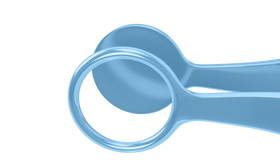

Rumex Lambert Chalazion Forceps, Medium, 12.00 mm Diameter, Length 97 mm, Titanium, 4-1909T

12.00 mm internal diameter of the upper plate. Designed to evert the eyelid. The ring blade surrounds the lump to expose chalazion for drainage and removal. Solid lower plate. Locking thumb screw mechanism.